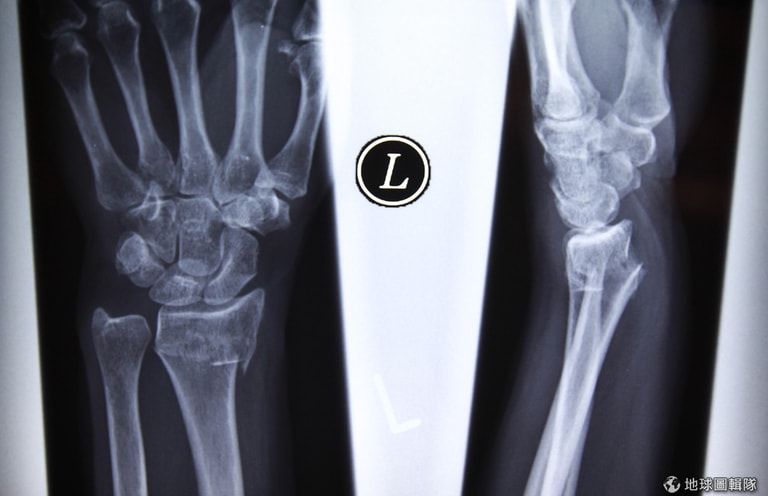

在驗證難民身分時,往往會碰上難民身上沒有證明文件可以佐證真實年齡的問題,這時,用X光攝影來檢測手腕的骨齡就是一種常用的方法。圖為一名手腕骨折患者的X光圖片。

關錯監獄的原因:X光攝影不太準

澳洲警察常用手腕X光攝影來比對年齡,法官會依據警察提供的骨齡攝影檢查數據來審判,但X光攝影未必準確。這些未成年的印尼人,因為法官採納骨齡檢查的結果,而在成人監獄裡面待上了好一段時間。